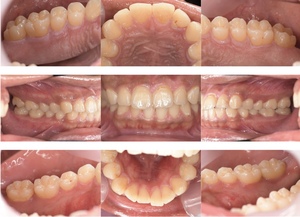

症例

症例1

Before

after

基本情報

年齢・性別 52歳・男性

主訴 主訴:久しぶりの歯医者なので歯石をとってほしい

治療部位:全顎

治療内容 1.歯磨き指導、歯肉縁上の歯石除去

2.歯磨きの確認、指導(磨けるようになるまで)

3.歯磨きの確認、指導、歯肉縁下の歯石除去(SRP)

4.PMTC

5.再評価、歯磨きの確認、指導

治療期間 1日

治療費 合計17,560円

・内訳

1、歯周基本検査・歯磨き指導、縁上スケーリング:1,800円

2、歯周精密検査・SRP(スケーリング・ルートプレーニング)、歯磨き指導:2,130円

3、SRP、歯磨き指導:3回(1,530円×3回)

4、PMTC、全顎再スケーリング、歯磨き指導:5,500円(自費診療)+1,260円

5、再評価(歯周精密検査)、歯磨き指導:2,280円

※PMTC以外、保険診療3割負担

(2023年5月現在現在)

リスク・副作用 ・毎日の歯磨きが不十分だと歯石を除去しても再度歯石がついてしまう

・最初は歯磨きのときに出血してくることがあるが、細菌が減って歯茎が引き締まってくると徐々に出血は落ち着いてくるため痛みがなければ辛抱強く磨いてもらう

・歯周病は時間をかけて静かに進行する病気なので、歯周病を治すにはそれなりに期間がかかる、すぐには治らない

・歯ぐきが引き締まると歯茎が下がり歯間に隙間ができる可能性がある

治療方針 一時的な治癒ではなく、将来的にこの治療が活かされるよう、患者さん自身である程度自己管理ができるようになることを目標とした

特記事項 ふつうのブラシと電動歯ブラシ使用(ブラウン丸型使)

歯間ブラシを1日1回は最低でも使って頂いた

担当者所見 あまり器用な方ではなかったため、決まったところがいつも磨けず奥歯に歯間ブラシがなかなか入れられませんでしたが、歯間ブラシのサイズを変えてみたり、内側から入れてみたりと試行錯誤してなんとかある程度磨けるようになりました。

その結果、出血が100%から7%へ激減することができました。

ただSRPをしただけではここまでの結果は出なかったと思います。

それほど日々のセルフケアが重要だということを再認識しました。

歯周ポケットが残っている部位、出血がある部位に関しては引き続き歯磨きを念入りに行なってもらう。